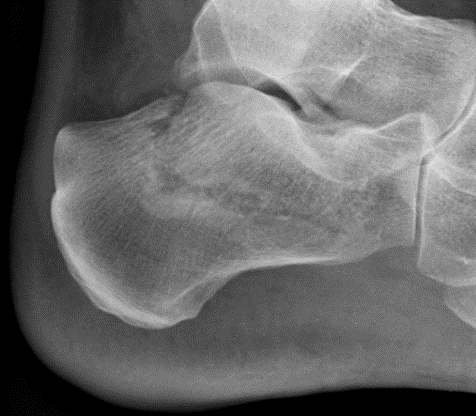

What type of fracture is this?

Segmental

Portions of bone must separate from the proximal and distal portion of the shaft of the bone